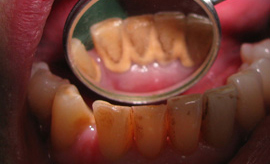

Zobni kamen nastane, ko se mehke bakterijske zobne obloge (plak) strdijo oz. mineralizirajo. Zobni kamen nad robom dlesni (supragingivalni zobni kamen) je obloga belo rumenkaste ali celo rjavkaste barve. Nastane najpogosteje na zobnih ploskvah ob izvodilih velikih žlez slinavk, in sicer na notranjih površinah spodnjih sekalcev (ob izvodilih podjezičnih slinavk) ter zunanjih površinah zgornjih kočnikov (ob izvodilih obušesnih slinavk). Zobni kamen nastaja tudi pod robom dlesni in enako pogosto na katerikoli ploskvi zoba in na vseh zobeh (subgingivalni zobni kamen). Lahko se vidi tudi na rentgenski sliki, če so obloge dovolj obsežne. Zobni kamen se nahaja v večini parodontalnih žepov, nastalih zaradi bolezni obzobnih tkiv. Zobni kamen je škodljiv, ker zaradi bakterij, ki jih vsebuje, povzroča vnetje dlesni in obzobnih tkiv, kar posledično pripelje do resorbcije kosti, majavosti in izgube zob.

Zobnega kamna v nasprotju z mehkimi oblogami ne moremo več sami očistiti s pripomočki za ustno higieno. Potrebno je profesionalno čiščenje trdih zobnih oblog v zobni ordinaciji, kjer običajno uporabljamo aparat s konico, ki vibrira v ultrazvočnem frekvenčnem območju. Po takem čiščenju zobe spoliramo, z gumicami, ščetkami in pasto s katerimi očistimo tudi razna zabarvanja s površine zob (čaj, kava, nikotin, barvila iz hrane in drugih pijač). Zobje postanejo svetlejši in gladkih površin, na katerih je težje nalaganje zobnih oblog. Čiščenje zobnega kamna je treba opraviti vedno, ko se obloge pojavijo, najmanj dvakrat na leto.

Zobni kamen je škodljiv, ker zaradi bakterij, ki jih vsebuje, povzroča vnetje dlesni in obzobnih tkiv (slike), kar posledično pripelje do resorbcije kosti, majavosti in izgube zob.